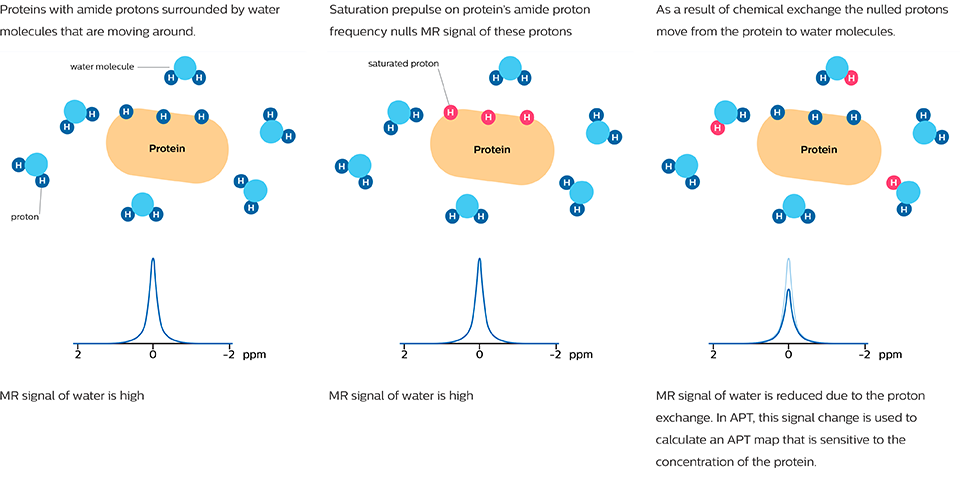

Amid Proton Transfer (APT)-gewichtete Bildgebung ist ein neues MRT-Verfahren, dessen Bildkontrast sich vom konventionellen MRT unterscheidet. APT-gewichtete Bildgebung ist ein MRT-Verfahren auf Grundlage des chemischen Austausch-Sättigungs-Transfers (CEST), und das Signal basiert auf der Konzentration von endogenen Proteinen und Peptiden, die typischerweise in hochdifferenziertem Hirntumorgewebe vorliegen. Daher erfordert APT-gewichtete Bildgebung kein Kontrastmittel mehr.

Bei der APT-gewichteten Bildgebung und anderen CEST-Verfahren wird das MRT-Signal durch einen anderen Mechanismus erzeugt als bei der klassischen MRT-Bildgebung. Diese CEST-Verfahren basieren auf dem chemischen Austausch von Wasserstoffatomen. Das Signal der Amid-Protonen von Peptidketten in Proteinen ist zu gering, um im normalen MRT gemessen werden zu können. Der Wasserstoff (Protonen)-Austausch zwischen Protein-Amidgruppen und umgebendem Wasser eröffnet eine andere Möglichkeit zur Messung dieser Amid-Protonen. Bei APT wird ein enger HF-Vorimpuls (Sättigungsimpuls) mit der Frequenz des Amid-Wasserstoffs abgegeben, um dessen MR-Signal abzuschwächen. Da die Amidgruppe und Wasser kontinuierlich Wasserstoffatome austauschen, steigt die Anzahl der gesättigten Protonen im Wasser, sodass das gemessene Wassersignal abnimmt. Die Veränderung des MR-Signals von Wasser ist eine indirekte Methode zur Messung des Vorliegens von Amiden. APT-Bilder werden normalerweise als eine durch Asymmetrieberechnung erstellte Farbskala dargestellt, wobei APT als positives Farbsignal dargestellt wird.